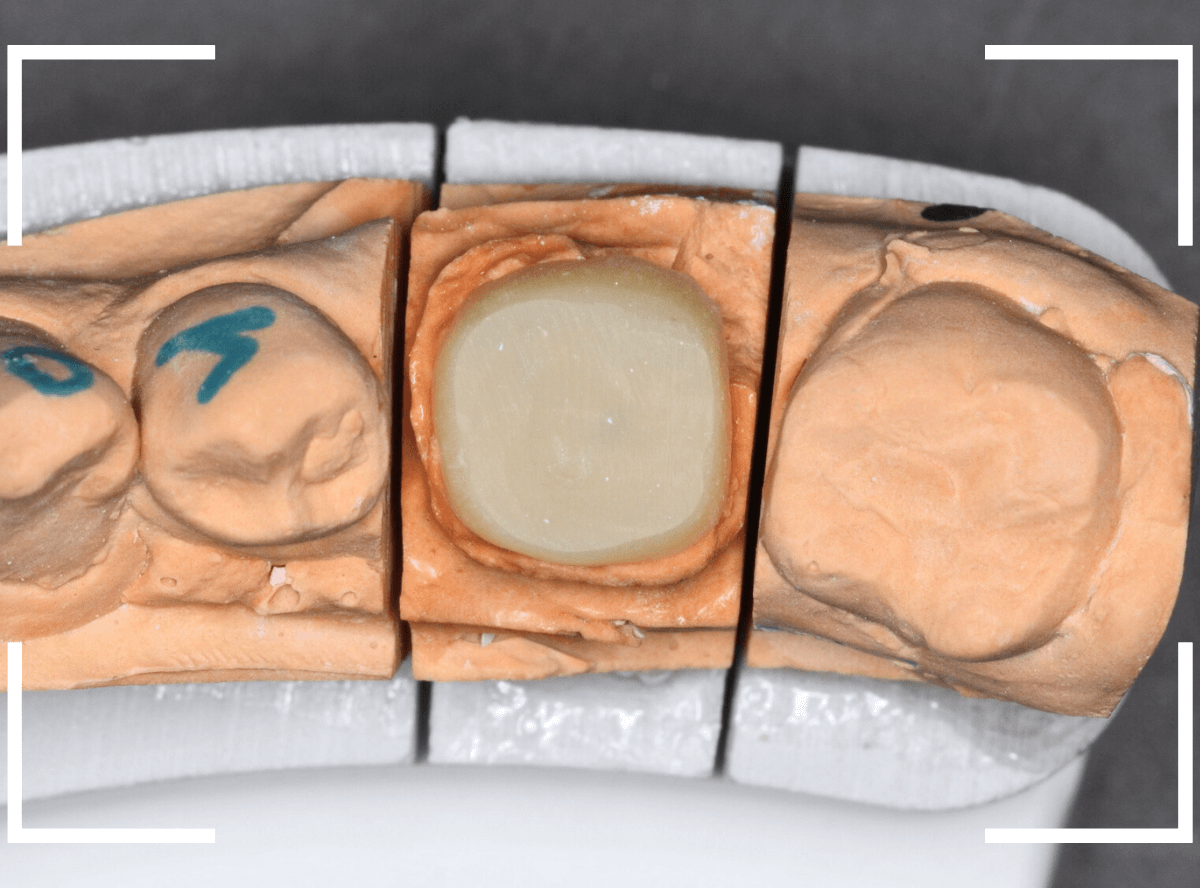

模型上で精密に製作します。

set後の写真です。